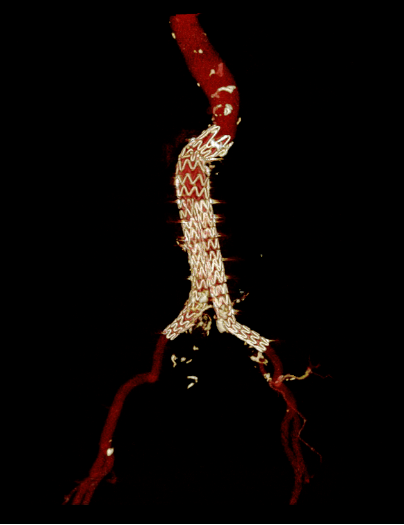

术后复查效果好

术后患者继续在SICU监护治疗,主治医师王德昌根据患者病情制定一系列切实有效的治疗措施,患者现已顺利脱机拔管。

在外科重症监护室给予加强肺部、肢体康复训练,病情逐渐稳定,现已转至普通病房,继续专科治疗,患者家属对外科重症监护室团队表示衷心感谢,称赞我们是挽救生命的“拆弹专家”。